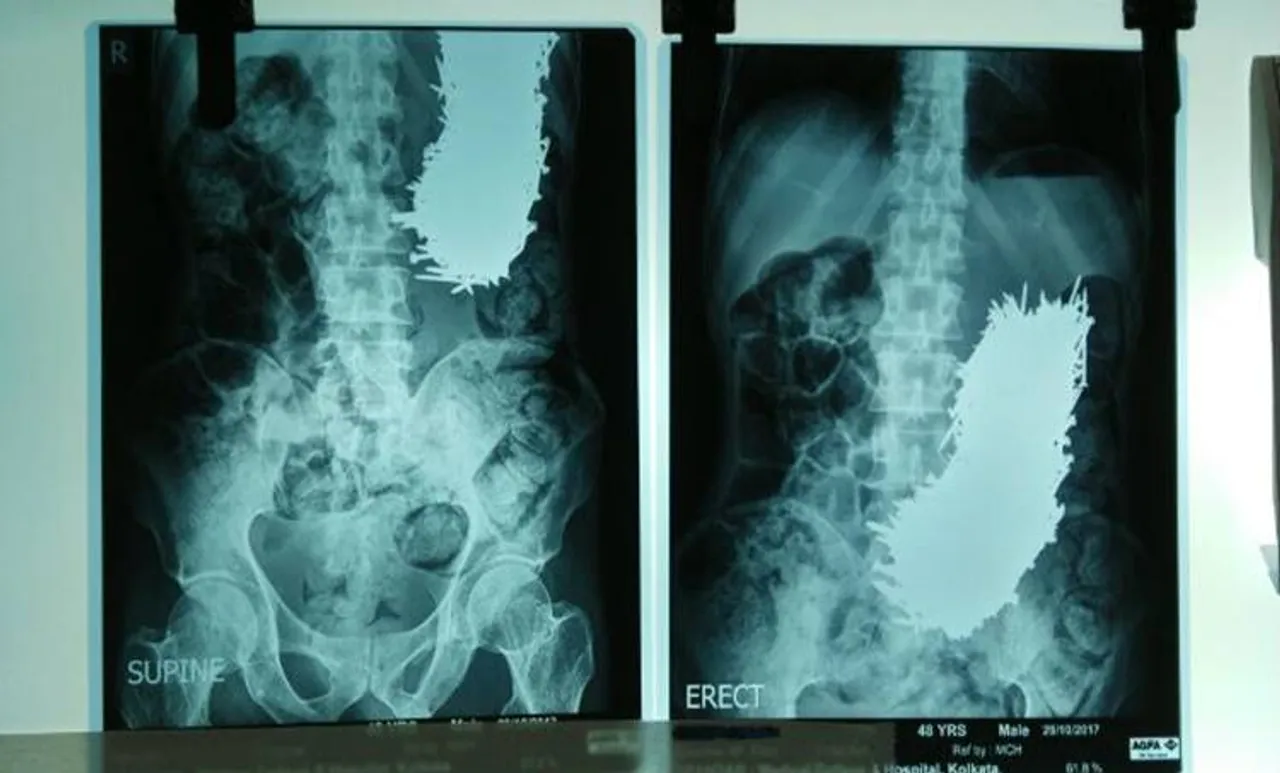

കൊല്ക്കത്ത: രോഗിയുടെ വയറ്റില് നിന്നും കാന്തം ഉപയോഗിച്ച് ഡോക്ടര്മാര് ആണികള് നീക്കം ചെയ്തു. കൊല്ക്കത്ത മെഡിക്കല് കോളേജില് രണ്ട് മണിക്കൂറോളം നടന്ന ശസ്ത്രക്രിയയ്ക്ക് ശേഷമാണ് 639 ആണികള് 48കാരന്റെ വയറ്റില് നിന്നും നീക്കം ചെയ്തത്. ഒരു കിലോഗ്രാമില് അധികം തൂക്കം വരുന്ന ആണികളാണ് ആമാശയത്തില് നിന്നും കണ്ടെടുത്തത്.

സ്കിസോഫ്രീനിയ എന്ന മാനസിക തകരാറുളളയാളാണ് രോഗി. വയറുവേദനയും ചര്ദ്ദിയും കാരണമാണ് ഇയാള് ഡോക്ടര്മാരെ സമീപിച്ചത്. എന്ഡോസ്കോപിയുടെ സഹായത്തോടെ ഇയാളുടെ വയറ്റില് ആണികള് ഉണ്ടെന്ന് മനസ്സിലാക്കുകയും എക്സ്റേ നടത്തി ഇത് സ്ഥിരീകരിക്കുകയും ചെയ്തു.

2.5 ഇഞ്ച് നീളമുളള 639 ആണികളാണ് ശസ്ത്രക്രിയയിലൂടെ പുറത്തെടുത്തത്. മിക്കതും വളഞ്ഞ രൂപത്തിലാണ് കണ്ടെത്തിയത്. ആമാശയത്തില് അഴുക്കും കണ്ടെത്തി. മണ്ണോട് കൂടിയ ആണികളായിരിക്കണം ഇയാള് കഴിച്ചതെന്ന് ഡോക്ടര്മാര് പറഞ്ഞു. ആണികള് എടുക്കാന് കാന്തമാണ് ഉപയോഗിച്ചതെന്നും രോഗിയുടെ നില ഇപ്പോള് തൃപ്തികരമാണെന്നും ഡോക്ടര്മാര് പറഞ്ഞു.